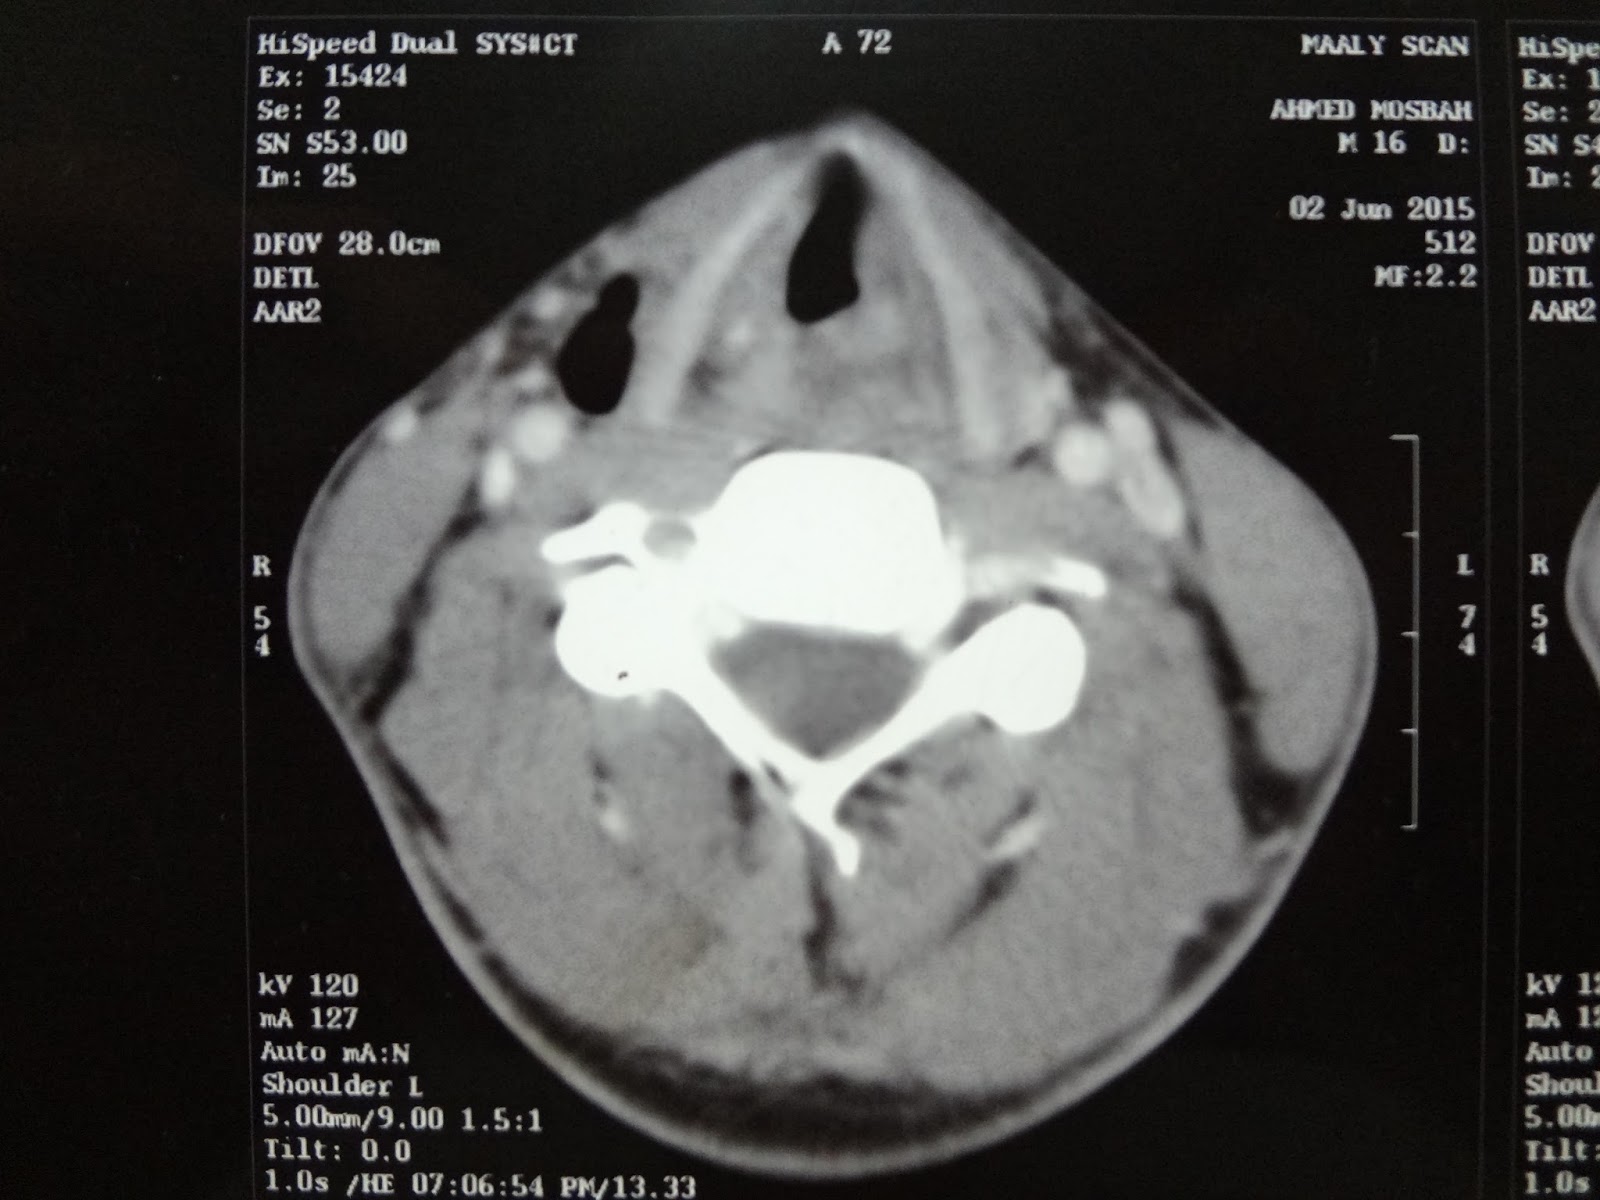

From rubbuy781.blogspot.com

laryngeal tracheal stenosis grade IV . UPPER airway stenosis due to Tracheal Stenosis In Endotracheal Intubation Thus, tracheal stenosis can most commonly occur following the two types of airway intubation: Tracheal stenosis is a common complication of endotracheal intubation or tracheostomy, resulting in significant morbidity. Tracheal stenosis, a common respiratory condition, is often caused by tumour or tuberculosis, or is a complication of intubation. Although infraglottic stenosis most commonly results from endotracheal tube damage, it may. Tracheal Stenosis In Endotracheal Intubation.